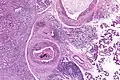

| Low magnification micrograph of a salivary duct carcinoma with characteristic comedonecrosis (left of image) adjacent to normal parotid gland (right of image). H&E stain. | |

Very low mag. -